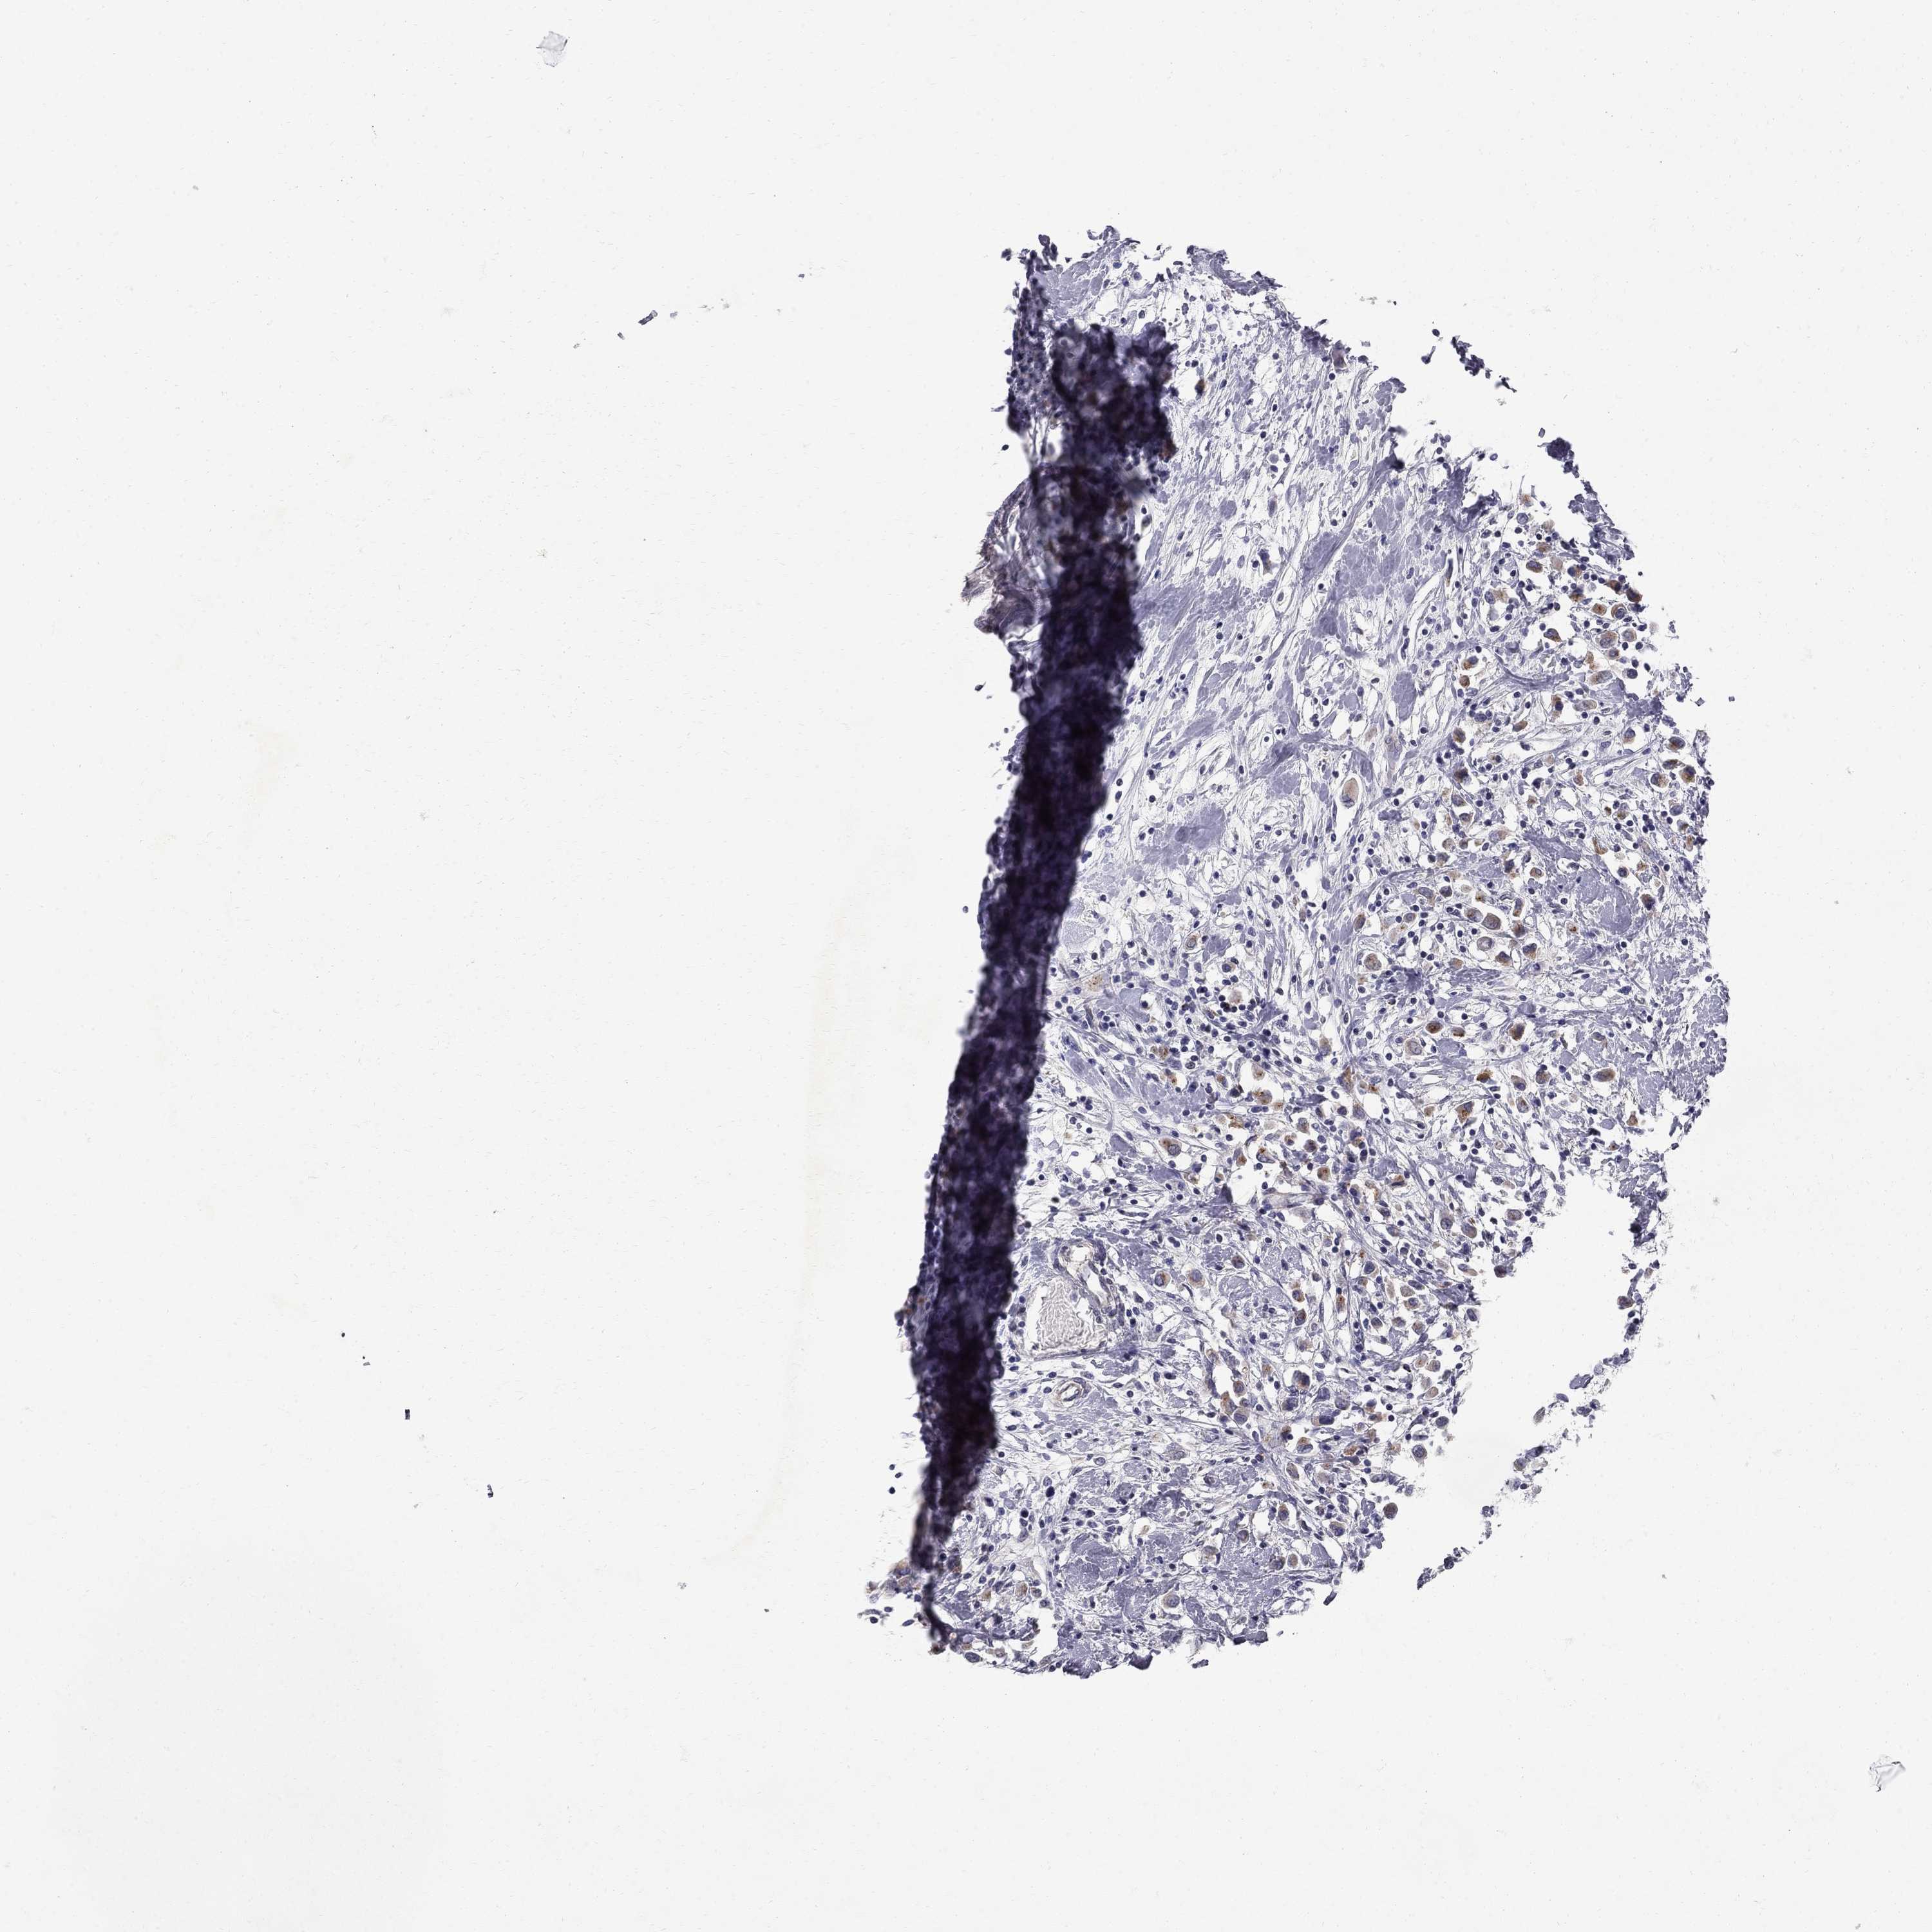

CANCER BREAST CANCER Show tissue menu

Breast cancer

Human cancer

CLIC6 is potential prognostic, high expression is favorable in Breast Invasive Carcinoma (TCGA)